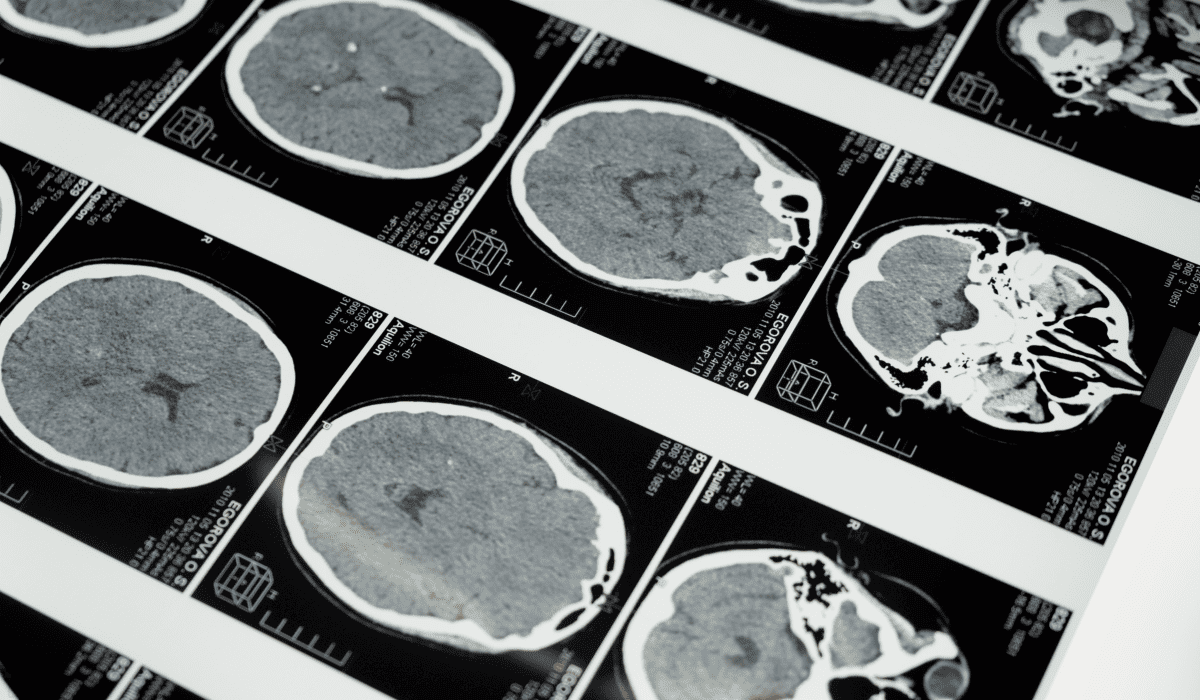

종합검진의 비용은 검진 항목 구성에 따라 크게 달라집니다. 일반적인 기본 검진은 20~30만 원 선에서 시작하며, MRI나 CT 같은 고가 장비가 포함되면 100만 원을 넘는 경우도 많습니다.

- MRI 포함형: 70~150만 원 이상

- 정밀형 PET CT: 200만 원 이상도 가능

- 뇌 MRI: 50~80만 원

- 복부 MRI: 70~120만 원

- PET CT(전신암검사): 150~250만 원

- 심장 CT: 40~60만 원